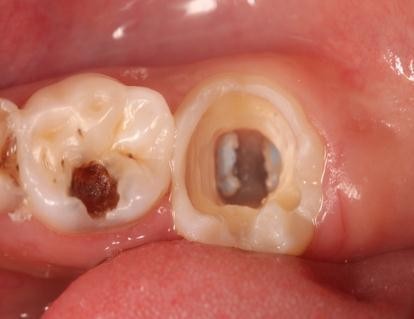

树脂修复病例

患者,女,右下6龋坏要求修复,平素体质一般,无药物、食物过敏史,无高血压、心脏病等系统病史。

去腐,树脂修复